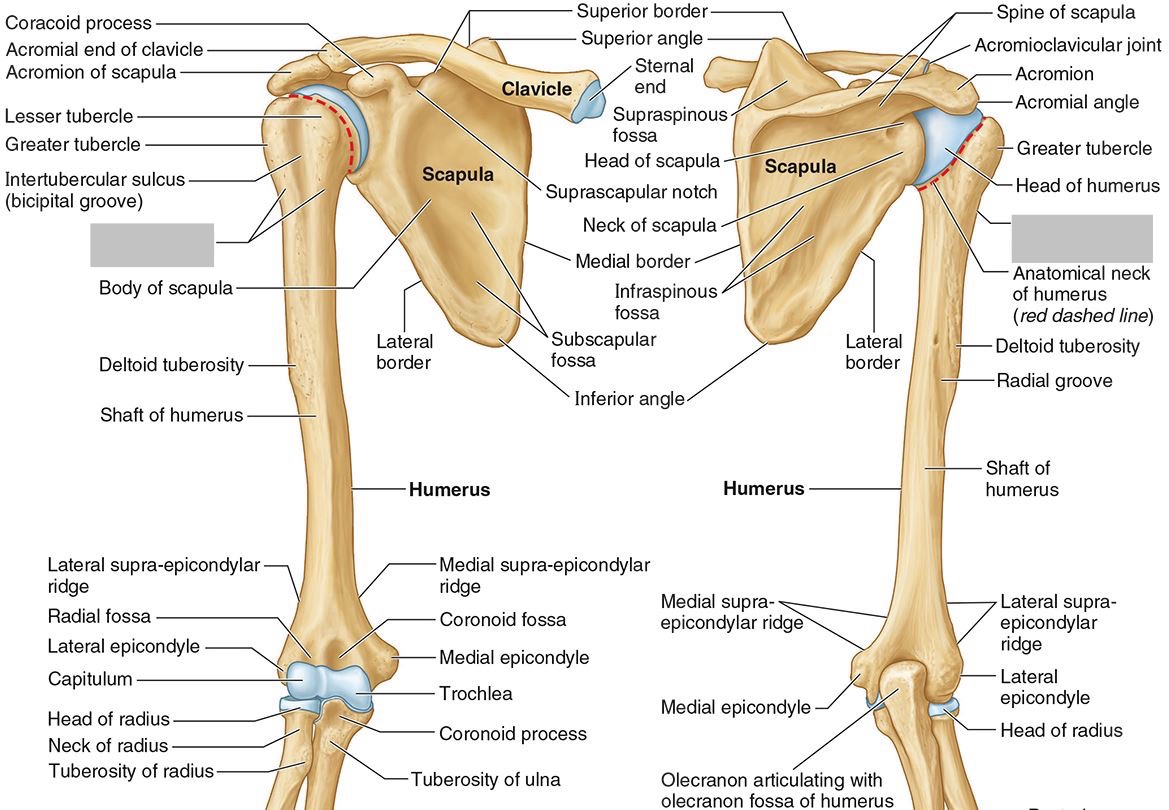

What part of the humerus is this?

The head of the humerus articulates with the scapula at the glenohumeral joint.

What part of the humerus is this?

The anatomic neck is an indentation distal to the head and provides an attachment for the fibrous joint capsule of the glenohumeral joint.

What part of the humerus is this?

The greater tubercle lies lateral and distal to the anatomic neck.

What part of the humerus is this?

The lesser tubercle lies on the anterior/medial side of the humerus, just distal the anatomic neck.

What part of the humerus is this?

The intertubercular (bicipital) groove lies between the greater and lesser tubercles.

What part of the humerus is this?

The surgical neck is a narrow area distal to the tubercles. It is a common site for proximal humerus fractures.

What part of the humerus is this?

The humeral shaft features the deltoid tuberosity laterally for the distal insertion of the deltoid muscle.

What part of the humerus is this?

The radial groove is an oblique depression that contains the radial nerve and deep brachial artery.

Which parts of the humerus is this?

The medial and lateral epicondyles are distal prominences to which many forearm tendons attach, near the elbow joint.

Which parts of the humerus is this?

The medial and lateral supracondylar ridges extend superiorly from the medial and lateral epicondyles.

Which parts of the humerus is this?

The trochlea and the capitulum (the condyles) are the most distal surfaces of the humerus, where it articulates with the forearm bones at the elbow joint

What part of the humerus is this?

The olecranon fossa is a posterior depression above the trochlea that receives that olecranon process of the ulna

What part of the humerus is this?

The coronoid fossa is an anterior depression above the trochlea that receives that coronoid process of the ulna.